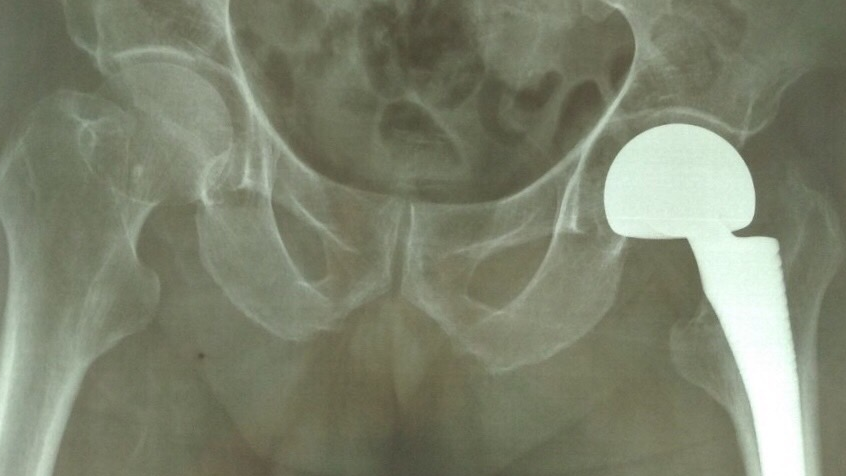

Phẫu thuật thay khớp háng nhân tạo nhằm loại bỏ phần cổ xương đùi bị gãy và thay vào đó bằng một khớp háng nhân tạo, từ đó bệnh nhân dần đi lại mà không đau và tránh được các biến chứng nguy hiểm với đối tượng người cao tuổi.

Phim chụp sau khi bệnh nhân được thay khớp háng thành công